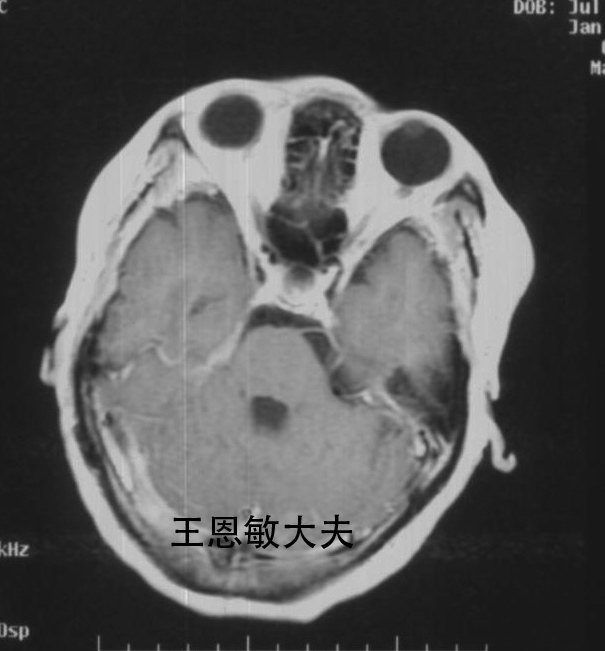

复发听神经瘤的射波刀治疗--每周一例